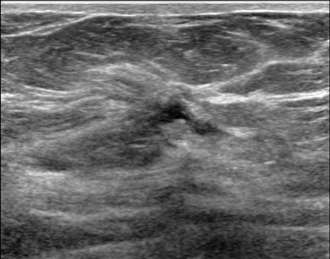

Hypoechoic mass with indistinct margins

The above ultrasound demonstrates a hypoechoic (dark) mass with indistinct margins, posterior shadowing, and distortion of the normal breast tissue. This was biopsied, revealing invasive ductal carcinoma (IDC). Both ductal carcinoma in situ (DCIS) and IDC may result in distortion.